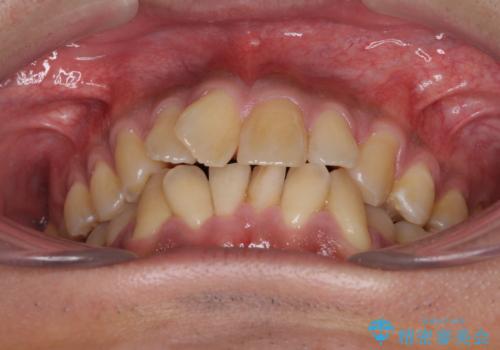

- 上下前歯の叢生を気にして来院された患者様です。

奥歯はクロスバイトとなっているので上顎は側方拡大を行いつつ、上下全体の叢生をインビザラインにより改善することとしました。